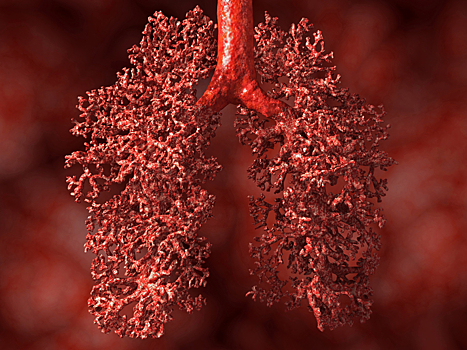

Ученые из Института Сэнгера и Университетского колледжа Лондона смогли доказать, что отказ от курение повышает уровень защиты организма от рака. В частности, уменьшается риск возникновения опухолей легких. Об этом сообщается в пресс-релизе на EurekAlert!.

По данным специалистов, результаты биопсии легких 16 пациентов показали, что между никогда не курившими людьми, а также бывшими и настоящими курильщиками существуют генетические различия.

Несмотря на то, что клетки злокачественными не была, в 9 из 10 клетках курильщиков были обнаружены до 10 тысяч мутаций - такое воздействие на организм оказывало употребление табака. Как минимум каждая четвертая мутация способствовала оразованию рака.

Тем не менее, у людей, которые бросили курить, было обнаружено в четыре раза больше здоровых клеток.